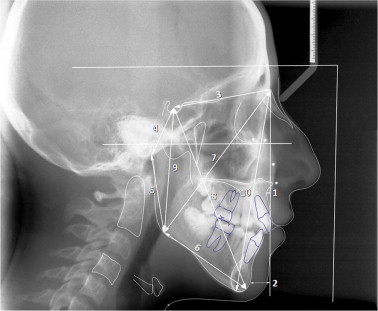

Figure 2.

(1) SNA angle (SNA), (2) SNB angle (SNB), (3) ANB angle (ANB), (4) Saddle/Sella angle (SN-Ar), (5) Articular angle, (6) Gonial/Jaw angle (Ar-Go/MP), (7) SN plane to mandibular plane angle (SN-MP), (8) Palatal-Mand angle (PP-GoGn), (9) Y-Axis, (10) SN-NPog, (11) NA-Apog (convexity), (12) FMA, (13) FMIA, (14) IMPA, (15) Mand Plane to Occ Plane (MP-OP).

Figure 3.

(1) A point to Nasion perpendicular (A to N perp), (2) Pogonion to Nasion perpendicular (Pog to N perp), (3) S-N: distance between sella and nasion point, (4) Posterior Cranial Base (S-Ar), (5) Ramus Height (Ar-Go), (6) Mandibular Body Length (Go-Gn), (7) Nasion-Gonion Length (N-Go), (8) Y-Axis Length (S-Gn), (9) Posterior Facial Height (S-Go), (10) Anterior Facial Height (Na-Me).

Figure 4.

(1) CVT-SN:angle between the CVT line and SN plane, (2) OPT-SN:angle between the OPT line and SN plane, (3) CVT-Hor: angle between the CVT line and horizontal line, (4) OPT-Hor: angle between the OPT line and horizontal line, (5) CVT-PP: angle between the CVT line and palatal plane, (6) OPT-PP: angle between the OPT line and palatal plane, (7) H-MP: distance to the H point measured perpendicular to the mandibular plane (MP), (8) H-Me: distance between the H point and menton, (9) H-MP: angle between the H-menton line and mandibular plane, (10) H-C4: distance between the H point and most inferior/posterior point on the fourth cervical vertebra corpus.

Twenty-seven measurements (15 angular and 12 linear) (Figs. 2 and 3) were used for craniofacial analysis (Table 2). Additionally, 12 measurements were evaluated to assess head posture (eight measurements) and the hyoid bone (four measurements) Fig. 4, as described in Table 2.